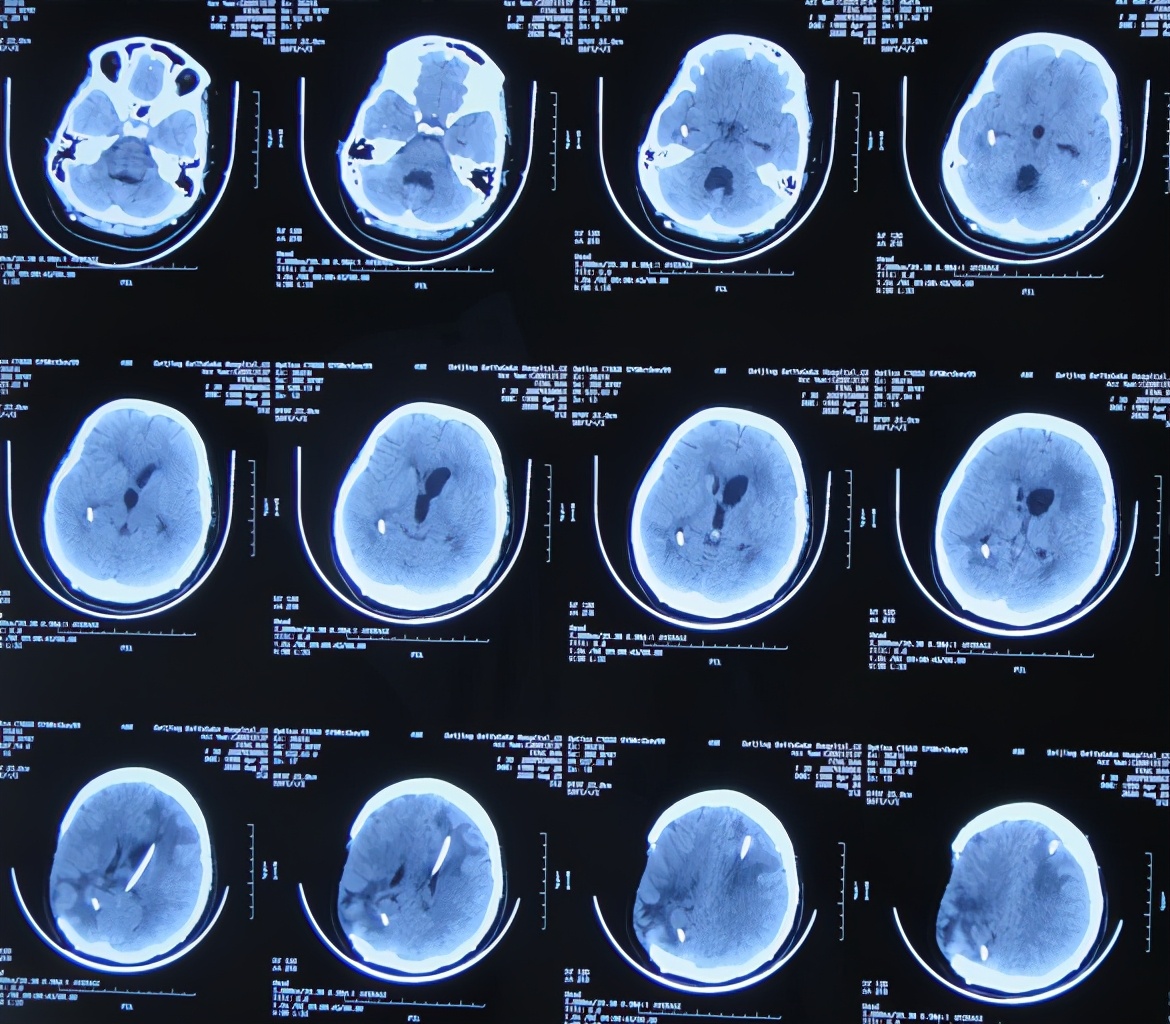

开颅术后40天2020年5月12日(腰大池引流管第4次脱出后19天),复查头颅CT示脑室持续扩大,轻度脑膨出( 图-6 )。

图-6: 2020年5月12日头颅CT

开颅术后49天2020年5月21日(腰大池引流管第4次脱出后28天),患者间断出现呕吐,骨窗脑组织膨出较前增加,复查头颅CT示脑积水脑膨出进一步加重( 图-7 )。医生建议转入上级的医院进行脑室腹腔分流术。

图-7: 2020年5月21日头颅CT